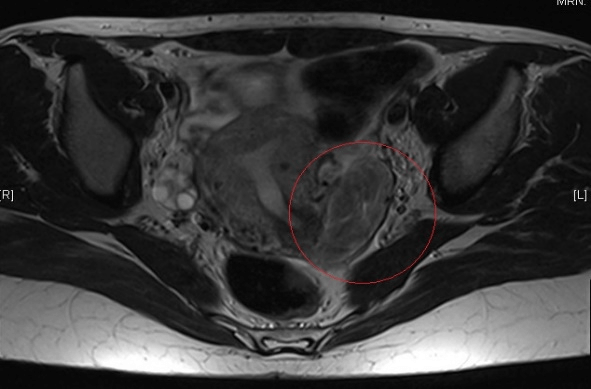

A-32-year-old patient, without medical or surgical history, allergic to penicillin and its derivatives, remitted to our consultation to study a retroperitoneal tumor shown in a vaginal ultrasound. From a digestive point of view, the patient was asymptomatic. She denied having nauseas or vomiting. She had a routine vaginal high-resolution ultrasound done that described a tumor which depends on the ovary, in the lower region of the uterus, towards the rectouterine pouch, with irregular edges, heterogenous content and calcifications about 51x29 mm with peripheric vascularization that suggested an ovarian teratoma. The uterus did not show any alterations except for a 11 mm subserous myoma. Neither ovaries presented alterations. She had a pelvic MRI, which showed a solid mass in the rectouterine pouch, shifted to the left, measuring 51x24x54 mm (CCxTxAP), hyperintense in T2 sequence and isointense in T1 sequence without signal loss in relation fatty tissue. A CT scan was performed also, and it did not show any pelvic adenopathy neither any changes as free liquid. (Figures 1 & 2). The patient had a normal abdominal exploration, with a tenderness abdomen, without pain and the tumor was not palpable.

Figure 1: MRI sequence.

The MRI and CT are useful to locate the tumor when planning the surgery. In these imaging techniques, the characteristics of parasitic myomas are also unspecific, but in the T2 sequence of MRI, has a lower signal, similar to smooth muscle [11]. The most frequent diagnosis of parasitic myomas are incidental findings during another abdominal surgery. The histopathology of the piece after the surgical resection is what confirms the definitive diagnosis. In our case, the patient had an exploratory laparoscopy to remove a retroperitoneal tumor under a suspected diagnosis of as teratoma, and it was the histopathology that gave the definitive diagnosis of parasitic myoma.